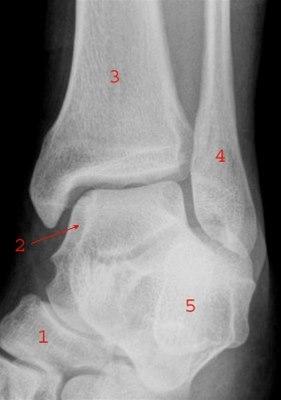

Ankelleddene er meget utsatte for skader fordi de er ganske bevegelige og belastes med hele kroppens tyngde. Det skilles et øvre og et nedre ankelledd. Det øvre ankelleddet utgjøres av tre ben: de nedre delene av skinnebenet (tibia) og leggbeinet (fibula), og ankelbeinet (talus). Det nedre ankelleddet dannes av tre ben: hælbeinet (calcaneus), ankelbeinet (talus) og båtbenet (os naviculare). Det er det øvre ankelleddet som denne artikkelen handler om. Leddet stabiliseres av ankelgaffelens form og leddbånd på innsiden (medialt), utsiden (lateralt) og mellom de to leggbeina (syndesmosen - et bånd som binder sammen de to beina). Se illustrasjon av ankelleddet nedenfor sett bakfra og fra siden, og røntgenbilde tatt skrått bakfra og fra siden.